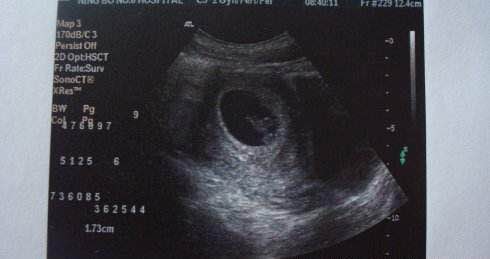

孕15周+4天